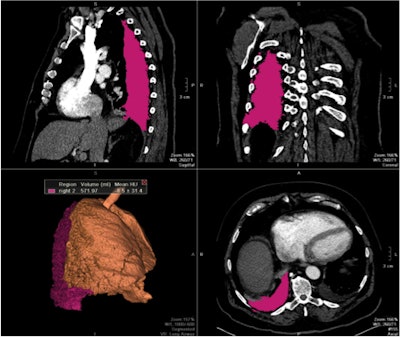

| Images show three traditional multiplanar reformatted reconstructions (MPRs) and one 3D reconstruction of final segmented pleural effusion volumes using a semiautomated quantification method (above) and manual method (below) on the same patient. The semiautomated segmentation method calculated a pleural effusion volume of 571.97 mL, a difference of less than 3% compared with 589.79 mL on manual segmentation. All images courtesy of Dr. Marcos Botelho. |